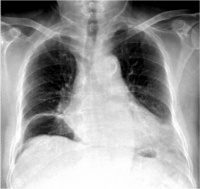

③x线检查:有选择的x线检查对腹部损伤的诊断是有帮助的。常用的有胸片、平卧位及左侧卧位腹部平片。立位腹部平片虽然更有意义,但不适用于重伤员。根据需要拍骨盆正、侧位片。

Bk8b8.jpg

• X线检查:常用胸片及平卧位腹平片

– 胃或肠管破裂à腹腔游离积气(如膈下)

– 腹膜后十二指肠或结直肠穿孔à腹膜后积气

– 肝破裂à右膈升高、肝正常外形消失、右下胸肋骨骨折

– 脾破裂à胃右移、横结肠下移、胃大弯有锯齿形压迹

大多数胃、十二指肠破裂和少数结肠、小肠破裂者,腹部平片显示膈下新月形阴影,提示有游离气体;侧卧位时的“穹窿征”和“镰状韧带征”,或仰卧位时的“双肠壁征”(在肠腔内外气体衬托下,肠管的内、外壁清晰可见),也是腹腔内积气的表现。为了提高阳性率,最好维持所需体位十分钟然后拍片。一般腹腔内有50ml以上游离气体时,X线片上便能显示出来。腹膜后十二指肠或结、直肠穿孔时,腹膜后有气体积聚,腹部平片上可见典型的花斑状阴影。肠间隙增大,充气的左、右结肠与腹膜脂肪线分离,是腹腔内积血量大的表现。腹膜后血肿时.腰大肌影消失。脾破裂时,可表现为胃向右移、横结肠向下移、胃大弯有锯齿形压迹(脾胃韧带内血肿)。右季肋部肋骨骨折、右膈抬高和肝正常外形消失,提示有肝破裂的可能。左侧膈疝时多能见到胃泡 或肠管突人胸腔。右侧膈疝诊断较难,必要时可作人工气腹以资鉴别。X线柱查可发现金属异物的部位,若与投射物的入口联系起来,可能有助于推测其在体内的轨迹以及可能伤及哪些脏器。 选择性血管造影对实质性器官破裂和血管损伤的诊断帮助很大。可见动脉相的造影剂外漏、实质相的血管缺如及静脉相的早期充盈。但血管造影要求的设备条件和技术条件较高,且属侵入性检查,有痛苦、费时和昂贵等缺点.绝大多数伤者不适合应用。